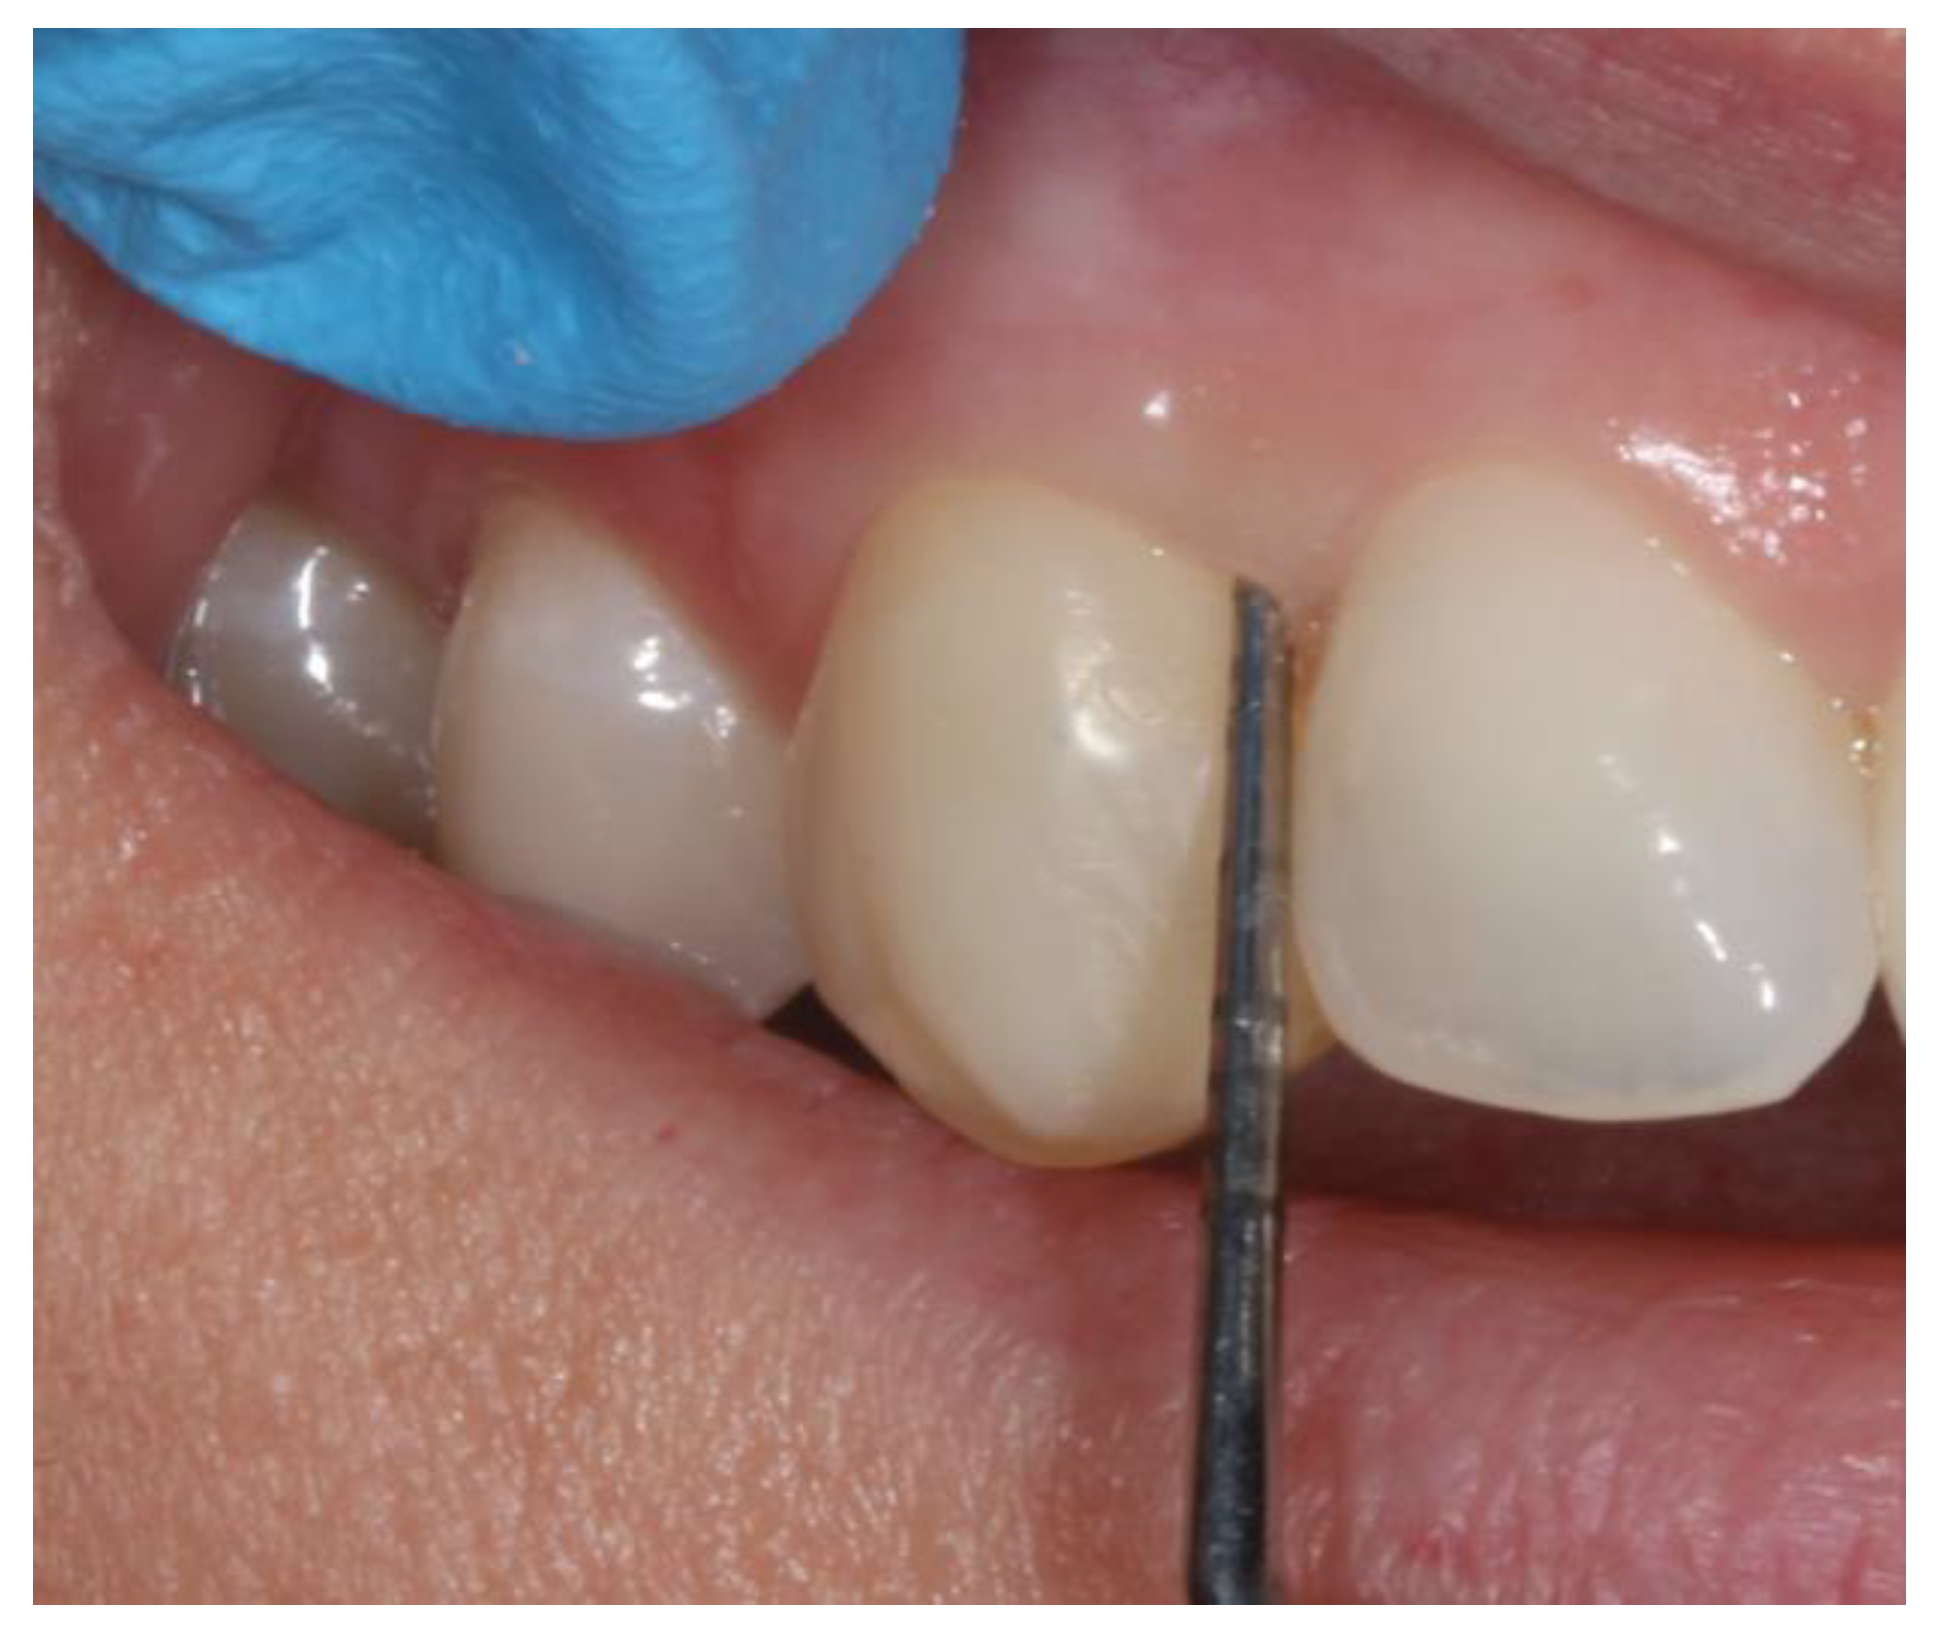

2.2. Clinical Variables